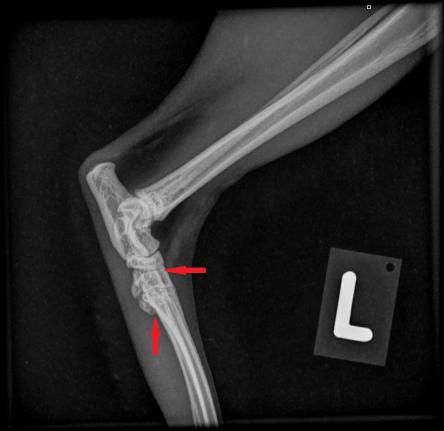

Die Besitzerin berichtet, dass der Kater recht lahmheitsfrei laufe, aber nicht über eine grosse Sprungkraft verfüge. Die Beine von Maxwell sind eher kurz und er scheint hinten und vorne X-beinig. Der Gang der Katze wirkt staksig; eine eigentliche Lahmheit ist nicht zu sehen. Um Aufschluss über die Situation in den Gelenken zu erhalten, werden die Vorderpfoten/Handgelenke, Hinterpfoten/Fusswurzelgelenke und die Wirbelsäule geröntgt. Es ist zu erkennen, dass Hand- und Fusswurzelgelenke gegenüber der Normalsituation eine X-beinigkeit (Valgisierung) aufweisen, an verschiedenen Stellen Anzeichen einer Arthrose vorhanden sind und insbesondere die Mittelhand- und Mittelfussknochen kurz und gedrungen erscheinen. Ein Teil der Fusswurzelknochen von Maxwell sind ausserdem zu einem einzigen Knochen verwachsen.

Sprunggelenk links Maxwell Sprunggelenk links normale Katze